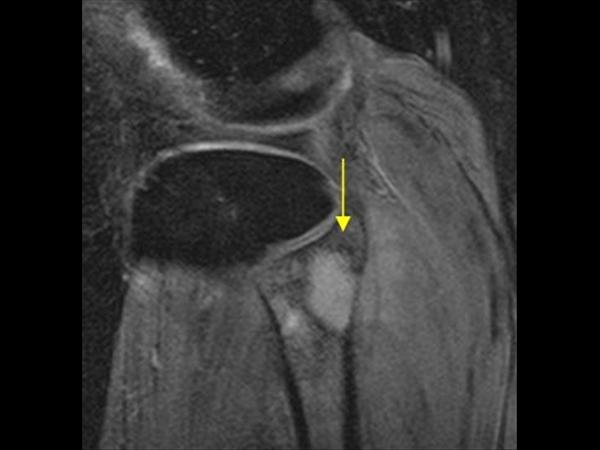

Apxe Brodie

Apxe Brodie + Mất liên tục màng xương

Apxe Brodie + Mất liên tục màng xương - Phù nề mô mềm

Viêm xương tủy

» Thông tin: Nam giới – 34 tuổi.

» Lâm sàng: Sưng đau khớp gối.

# Apxe Brodie / Mất liên tục màng xương – Phù nề mô mềm.